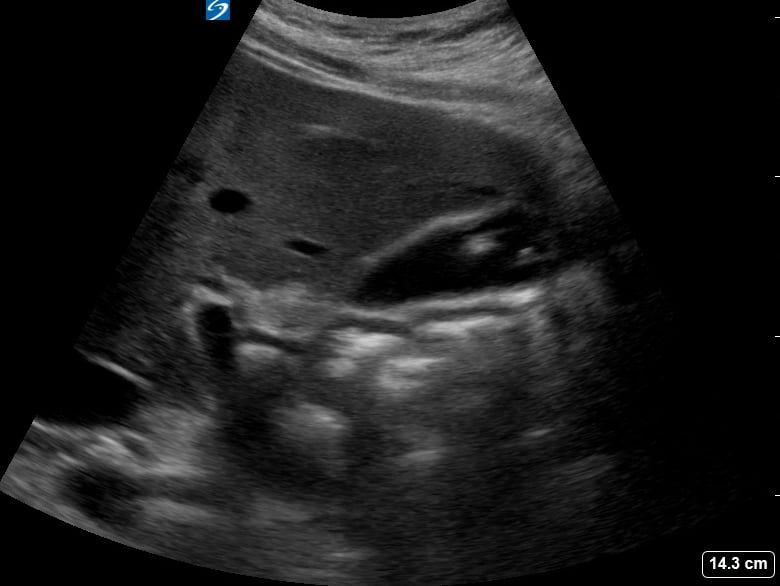

Gallstones are hardened deposits of digestive fluid that can form in the gallbladder, a small organ beneath the liver. In abdominal ultrasound, these concretions appear as hyperechoic structures within the gallbladder lumen, often with posterior acoustic shadowing. Their presence is a common finding during abdominal scans, frequently associated with symptoms like right upper quadrant pain, nausea, and vomiting, particularly after fatty meals.

Medical ultrasound plays a crucial role in diagnosing gallstones and related conditions such as cholecystitis (gallbladder inflammation) or choledocholithiasis (gallstones in the bile duct). Sonographic evaluation helps assess their size, number, and mobility, guiding clinical management and treatment decisions for patients experiencing abdominal discomfort or suspected biliary tract pathology.